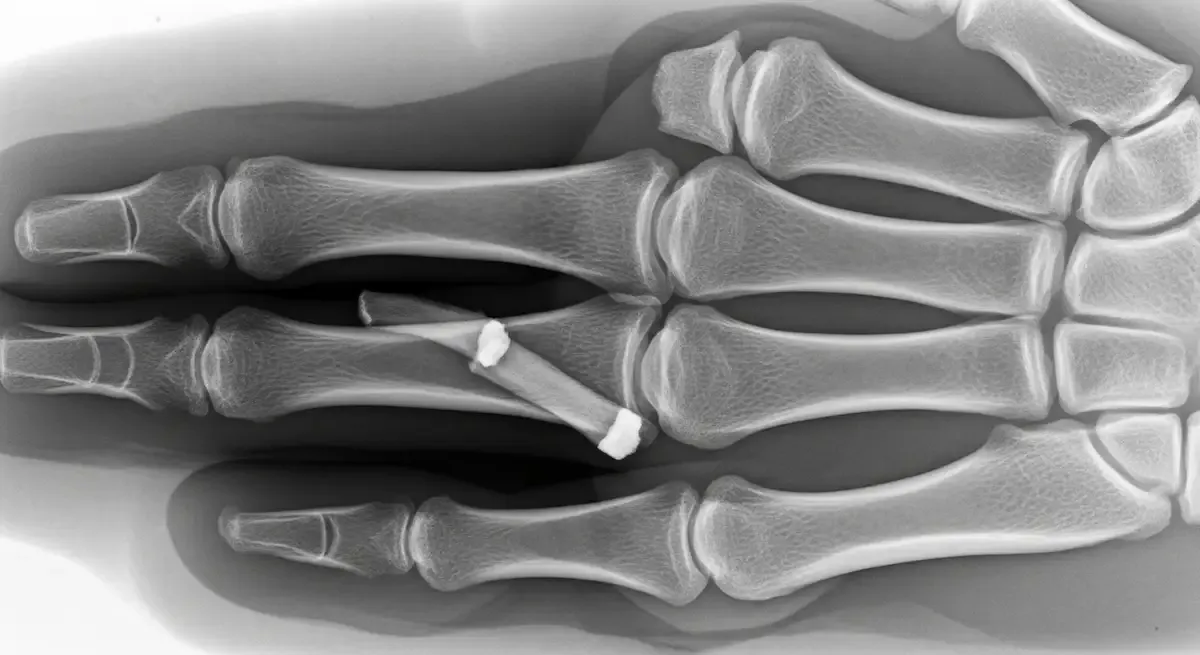

Torção No Dedo Da mão: O Que Fazer E Quando Tratar

A torção no dedo da mão é uma lesão frequente tanto em esportes quanto em situações do dia a dia. Um movimento brusco, uma pancada direta ou a rotação forçada do dedo já são suficientes para comprometer os ligamentos da articulação. Mesmo quando o...